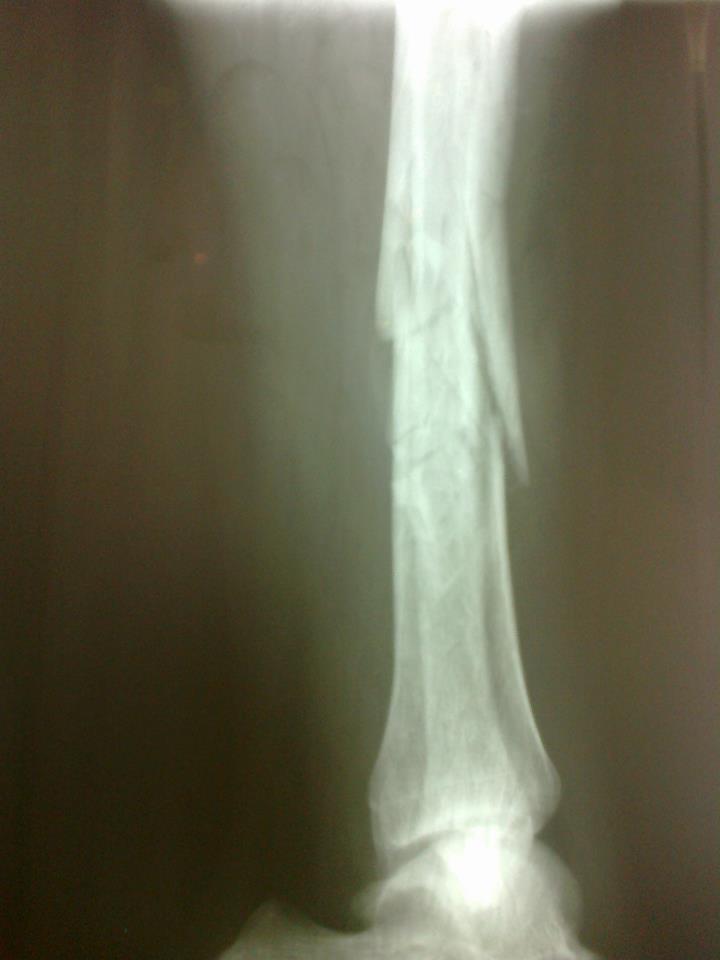

Здравствуйте, мне 27 лет, нахожусь в Таиланде, 6 мая в результате падения сломал правую ногу, врачи диагностировали открытый перелом обеих костей голени.

Доктора ближайшей больницы оказали первую помощь, сказали что нужна операция по восстановлению костей. По сраховке был направлен в другую больницу, где доктор-ортопед сказал, что сначала необходимо наложить гипс и ещё раз сделать рентген. После рентгена он сообщил, что кости встали на место и со временем срастутся. Теперь дело только в открытой ране, которая должна зажить без заражения на антибиотиках. Сейчас, 9 мая, лежу в больнице с гипсом на ноге, под капельницей(питательный раствор, несколько раз в день антибиотики), за это время успел по эл. почте проконсультироваться с врачем из прошлой поликлинники, который настаивает что при переломе обеих костей голени операция необходима. Подсказал, что подобное отношение к травме может быть навязано лечащей клинике страховой компанией, для сокращения затрат. Прошу помочь консультацией по вопросу - обязательна ли операция при таком переломе как у меня. Прикрепляю рентген перелома сразу после травмы и фотографию самой раны. Буду благодарен за любую помощь. http://i011.radikal.ru/1205/0c/41cb3c3da923.jpghttp://s019.radikal.ru/i606/1205/fb/515a9d98cbf6.jpg